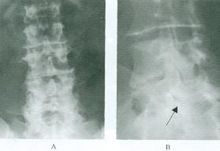

1.X线表现 骨关节的X线改变要在发病后2周方才显示出来,有时要1个月后才出现,在6个月以内属急性期改变;6个月以后为慢性期改变。急性期改变主要是受累关节周围软组织肿胀,骨质疏松,骨质破坏和关节损害。慢性期改变主要是骨质增生、硬化和关节强直,局部软组织肿胀表现为关节周围软组织密度增高、层次不清,皮下脂肪透明度减低;重者有网织状阴影,关节囊肿大,密度增高,轮廓多较清晰。这种改变是早期的主要所见,但不具特异性。慢性期软组织阴影缩小,且长期难以消失。少数病例在受累骨质邻近的软组织中出现小片状或团块状钙化或骨化阴影,骨关节方面的改变在早期是骨质疏松和骨小梁模糊或中断,局限于近关节的骨端,与类风湿关节炎的早期骨质疏松相似 急性骨质破坏往往在骨端的一侧或双侧有一个或多个小圆形虫蚀状破坏,边界清晰,常见于肌腱附着的骨隆突区。与此同时,附近可有单层细条状或不规则骨膜增生。本病后期的骨关节改变主要是在原来破坏区周围有骨质增生、硬化,破坏区边界清晰,致密,形成硬化致密的小环形灶,手、足管状骨常有整个骨干增粗,但无死骨。在骨骺未融合者,破坏区可在骨骺或干骺端,易引起骨骺早期闭合。关节间隙的改变表现为早期的关节间隙不对称狭窄、模糊,关节软骨面不平整,关节变形,甚至有半脱位,软骨下常有骨质破坏。在本病后期,可发现关节有自行融合趋势,可形成关节强直,但融合多不完全。2.其他影像学检查 CT及MRI检查及早发现早期骨关节改变。 -